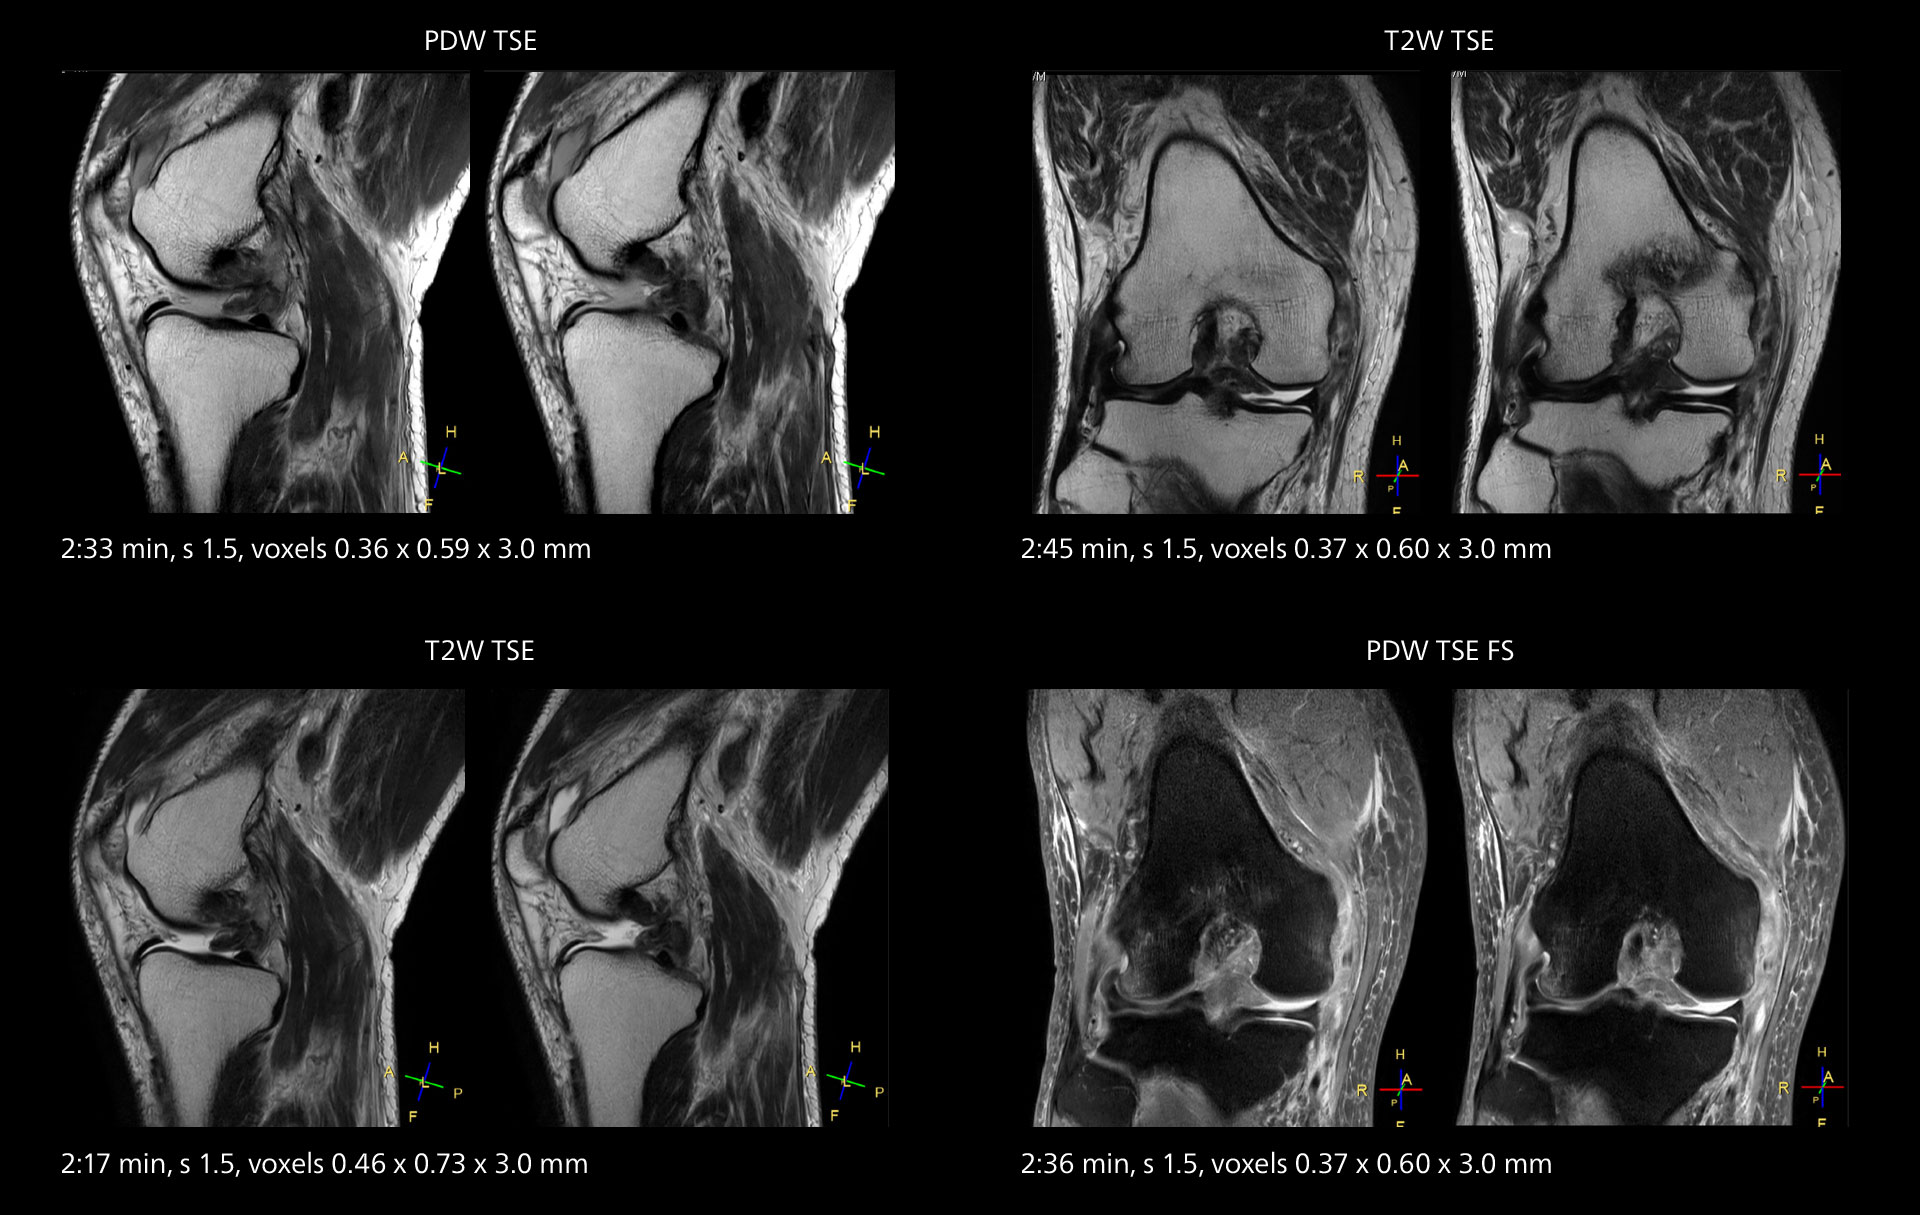

Images showing a posterior cruciate ligament (PCL) tear, a detached medial collateral ligament (MCL) on the tibial side and an intact anterior cruciate ligament (ACL). SmartPath to Elition X helped reduce scan time compared to previous imaging while maintaining resolution.

Sannodai Hospital radiologists had been very satisfied with their Ingenia 3.0T with Compressed SENSE, however after acquiring SmartPath to Elition X they have demonstrated improved image quality and even higher speeds in imaging studies throughout the body, according to Dr. Makuuchi. “Generally, we were impressed by seeing that images are very sharp and have higher SNR than we used to get with our Ingenia 3.0T system,” he notes. “We were delighted to see that high image quality can be obtained in a short time thanks to the Elition with its powerful An example of increased imaging speed is in knee studies. “There is a definite scan time reduction for T2* mFFE and proton density TSE – both of these sequences benefit from much shorter repetition times,” he reports.

Overall, imaging time per sequence has been reduced since the Elition X upgrade. This can help reduce the risk of patient movement and the need for rescans. “As our hospital has many elderly patients, we consider it important to obtain high-quality data in a short time,” Dr. Makuuchi says. “Shorter imaging times are also useful for accepting emergency patients, because faster emergency studies have a reduced impact on the daily examinations schedule. In emergency cases it is also important that high quality images are obtained in a short time.”